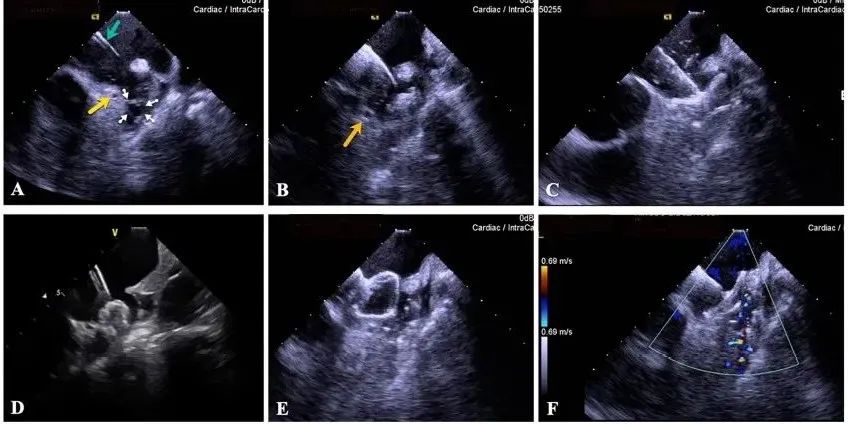

一種與心導(dǎo)管檢查相結(jié)合的超聲心動(dòng)圖診斷新興技術(shù),通過將超聲探頭置于心腔內(nèi)部,發(fā)射并接收超聲信號(hào),來(lái)精確獲取心臟解剖結(jié)構(gòu)、心臟血流動(dòng)力學(xué)等信息的實(shí)時(shí)成像。與其他影像技術(shù)相比,ICE技術(shù)具有操作簡(jiǎn)單、無(wú)輻射、安全性高、手術(shù)效率高、實(shí)用等優(yōu)勢(shì),ICE在很大程度上有望取代經(jīng)食道超聲心動(dòng)圖(TEE),成為電生理和結(jié)構(gòu)性心臟病領(lǐng)域的理想成像方式。

目前ICE技術(shù)已被應(yīng)用于左心耳封堵、房顫射頻消融、二尖瓣成形、房間隔缺損封堵等多種心臟介入手術(shù),應(yīng)用場(chǎng)景主要圍繞心臟電生理、結(jié)構(gòu)性心臟病等領(lǐng)域,目前以電生理應(yīng)用為主。數(shù)據(jù)顯示,我國(guó)結(jié)構(gòu)性心臟病介入器械市場(chǎng)規(guī)模已從2017年的4億元增長(zhǎng)至2021年的20億元,年復(fù)合增長(zhǎng)率達(dá)48.3%;預(yù)計(jì)到2025年,該市場(chǎng)規(guī)模將達(dá)到104億元,可以預(yù)見ICE市場(chǎng)規(guī)模也將同步高速增長(zhǎng),未來(lái)市場(chǎng)發(fā)展空間廣闊。

心腔內(nèi)超聲(ICE)技術(shù)壁壘極高,國(guó)內(nèi)主要廠商核心部件仍舊為進(jìn)口,集成了超聲和圖像處理最前端技術(shù),包括超聲探頭、線纜、軟件成像算法等,是當(dāng)前內(nèi)窺超聲方向最具挑戰(zhàn)的領(lǐng)域。ICE的應(yīng)用經(jīng)歷了2D平面成像、3D三維立體成像、以及4D的實(shí)時(shí)三維立體成像階段。